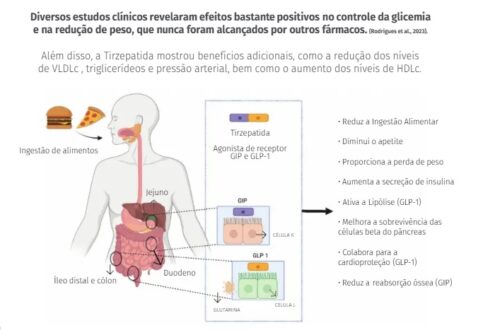

A tirzepatida (princípio ativo do medicamento Mounjaro, e também comercializada como Zepbound em alguns países) é um medicamento inovador usado principalmente para o tratamento de diabetes mellitus tipo 2 e, mais recentemente, para o controle do peso corporal (obesidade e sobrepeso).

Como Funciona:

A tirzepatida é um agonista duplo dos receptores GIP (polipeptídeo inibitório gástrico) e GLP-1 (peptídeo-1 semelhante ao glucagon), imitando a ação de dois hormônios intestinais naturais. Essa ação dual potencializa seus efeitos:

- Aumento da Insulina: Estimula o pâncreas a produzir mais insulina de forma dependente da glicose, o que ajuda a diminuir o açúcar no sangue.

- Redução da Glicose Hepática: Diminui a quantidade de açúcar produzida e liberada pelo fígado na corrente sanguínea.

- Controle do Apetite: Atua no cérebro (hipotálamo), aumentando a sensação de saciedade e reduzindo o apetite e a ingestão calórica.

- Retardo da Digestão: Desacelera o esvaziamento gástrico, o que contribui para a sensação de plenitude e ajuda no controle do peso.